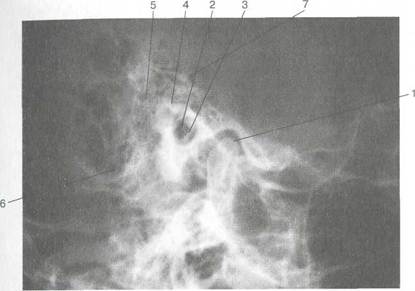

Рис. 1.5. Задняя риноскопия (эпифарингоскопия). а — положение носоглоточного зеркала; б — картина носоглотки при задней риноскопии: 1 — сошник, 2 — хоаны, 3 — задние концы нижней, средней и верхней носовых раковин, 4 — глоточное отверстие слуховой трубы, 5 — язычок, 6 — трубный валик.

должна быть направлена кверху. Затем заводят зеркало за мягкое небо, не касаясь корня языка и задней стенки глотки. При легких поворотах зеркала осматривают носоглотку (рис. 1.5).

12. При задней риноскопии нужно осмотреть свод носоглотки, хоаны, задние концы носовых раковин, глоточные отверстия слуховых (евстахиевых) труб. В норме свод носоглотки у взрослых людей свободный, слизистая оболочка розовая, хоаны свободные, сошник по средней линии, слизистая оболочка задних концов носовых раковин розового цвета с гладкой поверхностью, концы раковин не выступают из хоан, носовые ходы свободные.

На боковых стенках носоглотки на уровне задних концов нижних носовых раковин имеются небольшие углубления — глоточные отверстия слуховых труб.